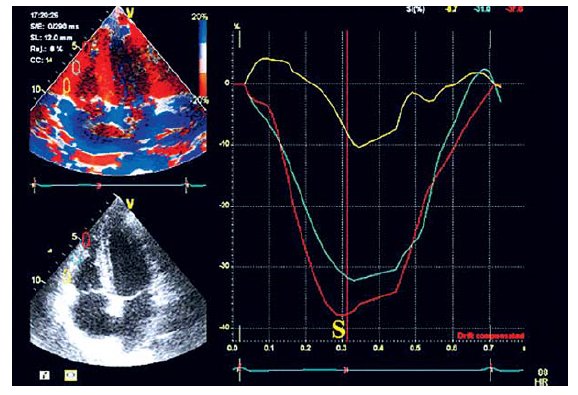

С помощью тканевого допплера можно измерить локальную систолическую скорость движения миокарда (S’), деформацию (S) и скорость деформации (SR) в сегментах свободной стенки ПЖ (рис. 5–7).

Рис. 5. Измерение S’ в базальном, срединном и верхушечном сегментах свободной стенки ПЖ

Рис. 6. Измерение S в базальном, срединном и верхушечном сегментах свободной стенки ПЖ

Рис. 7. Измерение SR в базальном, срединном и верхушечном сегментах свободной стенки ПЖ